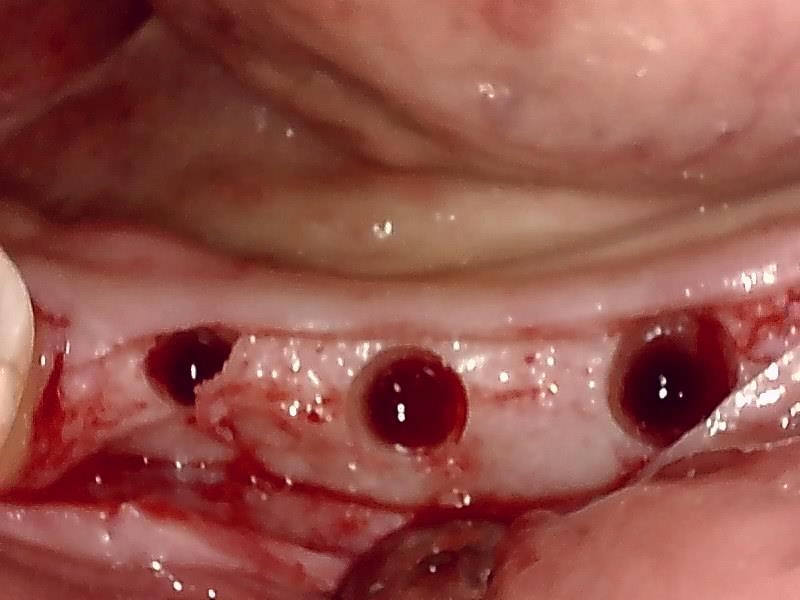

顎堤部 歯槽骨にドリリングする。

インプラント体の口径に合わせて埋入孔を形成した状態です。

術中インプラント埋入した状態は良好です。

自家骨移植 GBR を施す。理想的な顎堤に築造する。